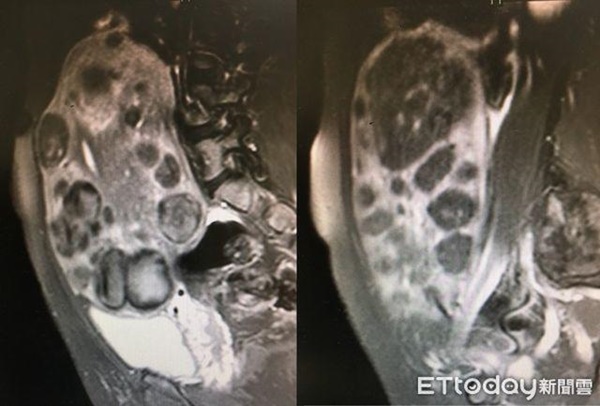

Bác sĩ Trịnh Thừa Kiệt, Giám đốc điều hành của Trung tâm điều trị Hải Phù Đao, thuộc Bệnh viện Bác Nhân Đài Bắc. Đồng thời ông cũng là giáo sư Phụ sản của Đại học y Cao Hùng. Trong cuộc phỏng vấn với Ettoday, bác sĩ Trịnh đã chia sẻ về trường hợp người phụ nữ 48 tuổi – cô Vương, được chẩn đoán có hơn 100 khối u lớn nhỏ ở tử cung, trong đó khối u lớn nhất là 19cm, khối u nhỏ thứ 2 là 12cm, có 90 khối u có kích thước 2cm.

Các khối u này đã tồn tại cách đây hơn 10 năm, nguyên nhân khiến cô Vương trì hoãn bệnh chính là cô sợ phẫu thuật, và cô còn nghe nói “khi bị mãn kinh thì các triệu chứng sẽ cải thiện, khối u xơ sẽ dần dần co lại”. Tuy nhiên, cô không thể đợi đến ngày mãn kinh, các khối u càng ngày càng lớn, cộng thêm thời gian dài lượng kinh nguyệt ra nhiều, điều này khiến cô Vương rất khổ sở, mỗi ngày cô phải thay hơn 10 miếng băng vệ sinh, mỗi lần cô đi ra ngoài đều cảm thấy rất bất tiện. Mặc dù thời gian dài cô còn bổ sung thuốc bổ máu, nhưng lượng hemoglobin cũng chỉ còn 7gm/dl.

Theo bác sĩ Trịnh Thừa Kiệt, mãi đến khi cô Vương đến trung tâm Hải Phù Đao tiến hành phẫu thuật cắt bỏ u xơ tử cung. Sau phẫu thuật tình trạng xuất huyết và các triệu chứng tiết niệu nhanh chóng được cải thiện. Sau một năm tái khám, bác sĩ phát hiện số lượng u xơ đã giảm đi một nửa, thể tích cũng thu hẹp đến 8 phần, hầu hết các triệu chứng đã biết mất, điều quan trọng hơn là cô Vương đã giảm được 10cm vòng eo và giảm được 6kg.